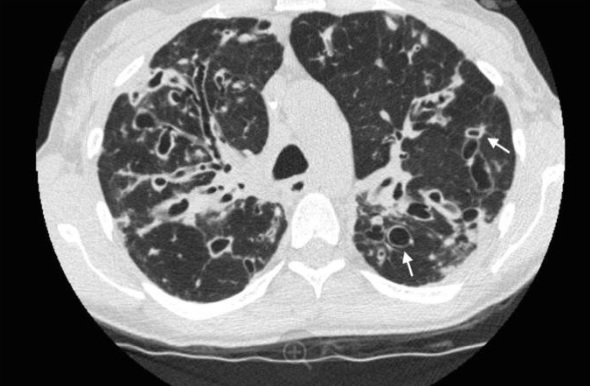

¿Cuál es el diagnóstico?

Consolidación vidrio esmerilado y empedrado loco.